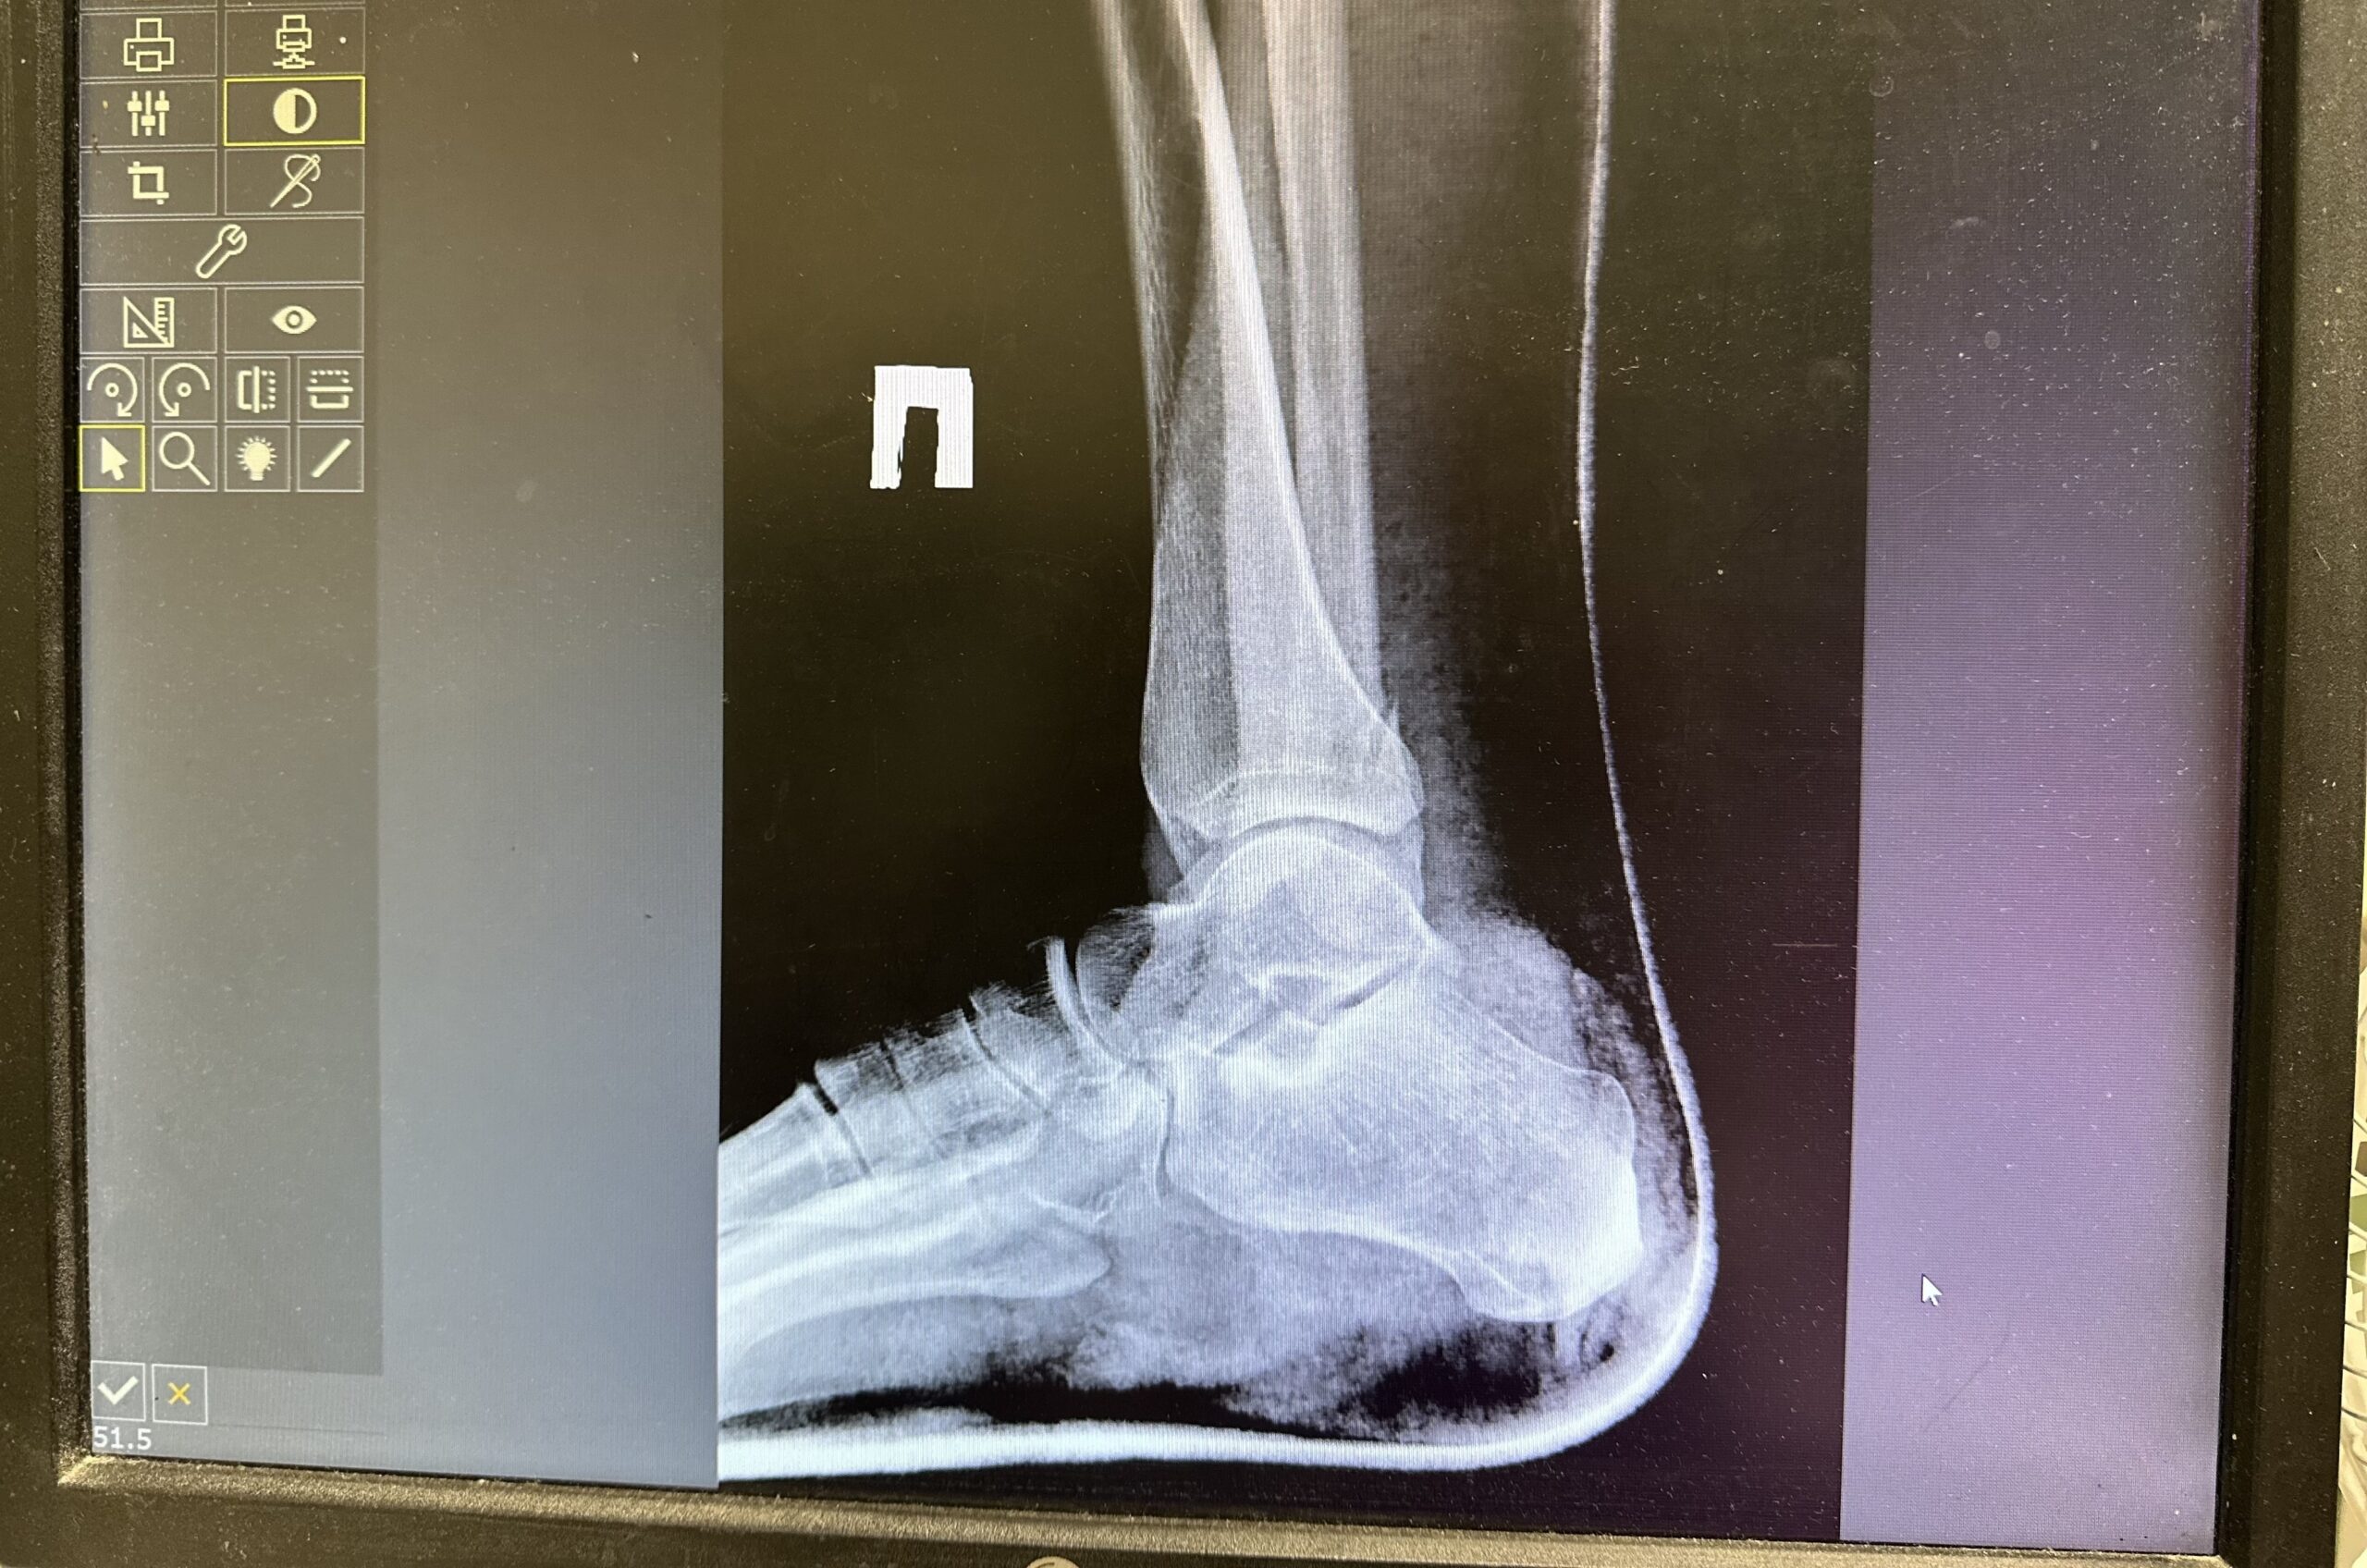

В Пермском крае суд вынес приговор местной жительнице, которая во время конфликта избила новую сожительницу своего бывшего супруга. В результате потерпевшая получила множественные переломы обеих ног, сообщили в Пермском краевом суде.

Инцидент произошел во время имущественного спора. Женщина в сопровождении подруг приехала к бывшему мужу, чтобы забрать вещи, которые пропали с ее дачи после развода. В ходе ссоры она избила новую сожительницу бывшего супруга, вышедшую на шум. В результате потерпевшая получила множественные переломы обеих ног.